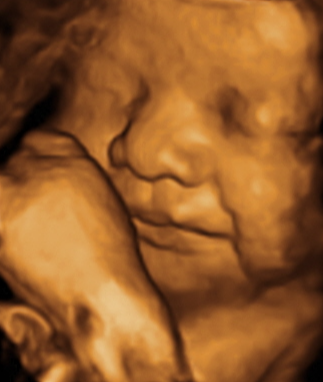

정상 자세로 돌아온 후엔 얼굴도 평온해 보이고 ㅋㅋ 더 이상 얼굴 옆에 다리가 보이지 않고 왼쪽 얼굴이 보였어요!